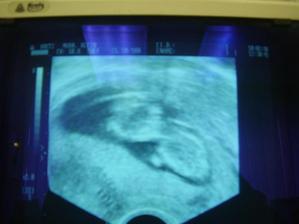

NÁŠ DRUHÝ POKLADÍK